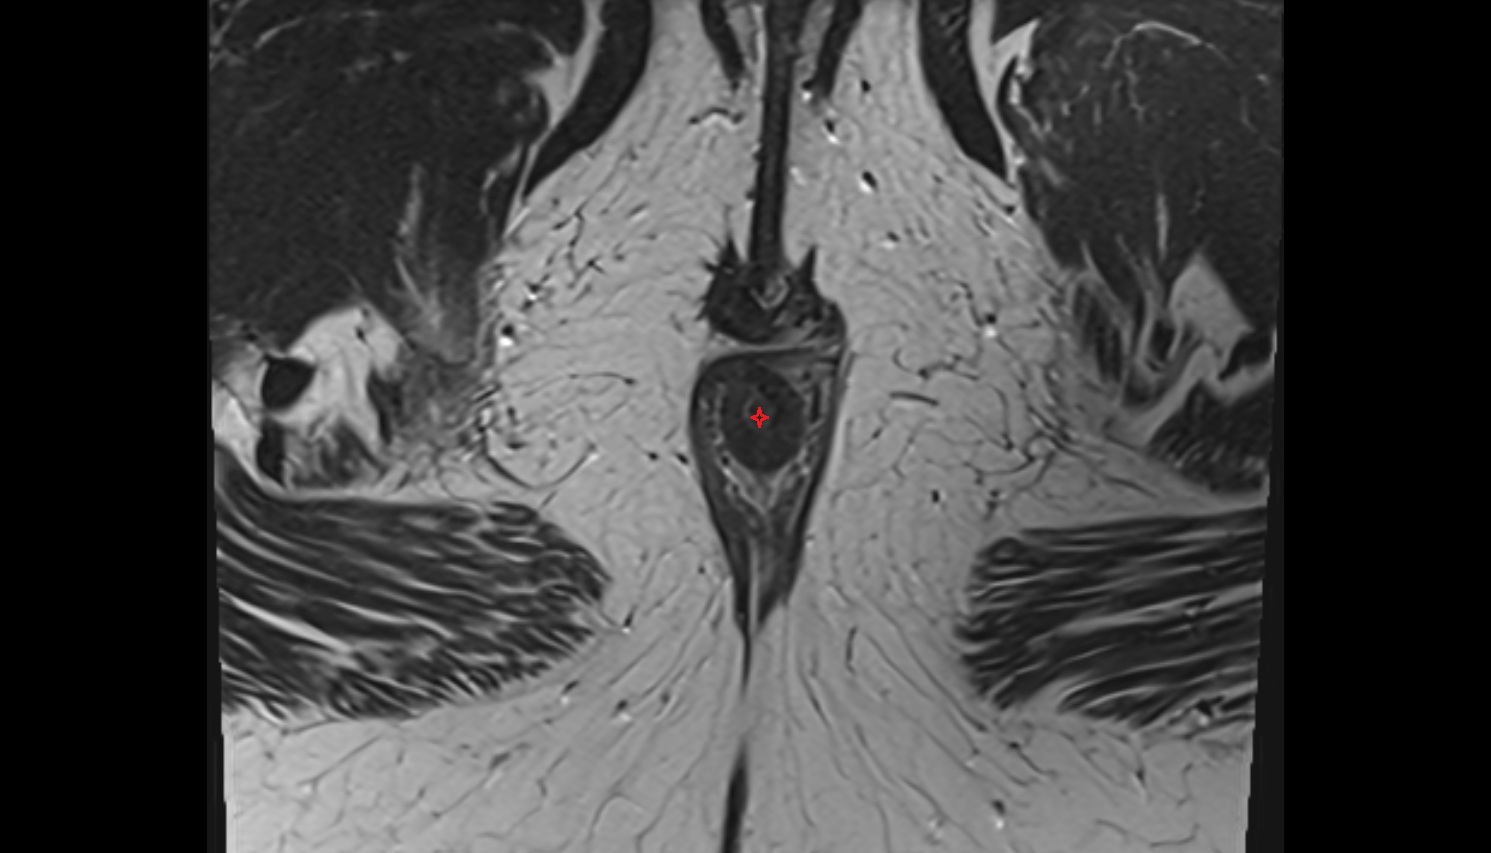

- Corpus cavernosum

- Corpus spongiosum

- Bulb of Penis

- Crus of penis

- Buck's fascia (Deep fascia of penis)

- Dartos fascia

- Areolar tissue of penis

- Septum of the penis (Penile septum)

- Glans penis

- Corona of glans penis

- Coronal sulcus